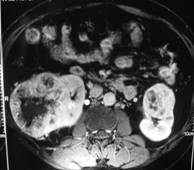

病症檢查

在腎動脈血栓或栓塞危險因素的病人出現可疑症狀和體徵時,就要疑及此病,作進一步檢查雖然血清酶學(血清穀草轉氨酶GOT、LDH及血清鹼性磷酸酶AKP)化驗對診斷有幫助但無特異性確診仍需腎臟影像學檢查,尤其是選擇性腎動脈造影。